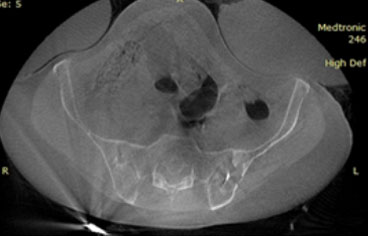

Kötü huylu kemik tümörlerinde ise sıklıkla kemik metastazı dediğimiz başka bir organdan kaynaklanan kanserin kemiğe sıçradığı durumlarda tercih etmekteyiz.

RF ablasyon işlemi bittikten sonra aynı giriş kanülünden kapalı çimento uygulaması özellikle omurga (vertebra) ve pelvis/asetabulum metastazlarında mekanik ve ağrı açısından ekstra avantaj sağlar. RF ablasyon çimentonun kemik içerisine daha homojen yayılmasına olanak sağlar. Bu yöntem kırık gelişmiş ya da kırık riski olan omurga kemiklerine (instabilite ve ciddi omurilik basısı durumunda önerilmez) uygulanabilir. Ablasyon işleminin tamamlanmasının ardından kemik çimento enjeksiyonu uygulanacak ise, doku ısısının düşmesi ve aşırı ısınmaya bağlı hasar gelişme ihtimalini önlemek amacıyla yaklaşık 15 dakika beklenmesi gerekir.